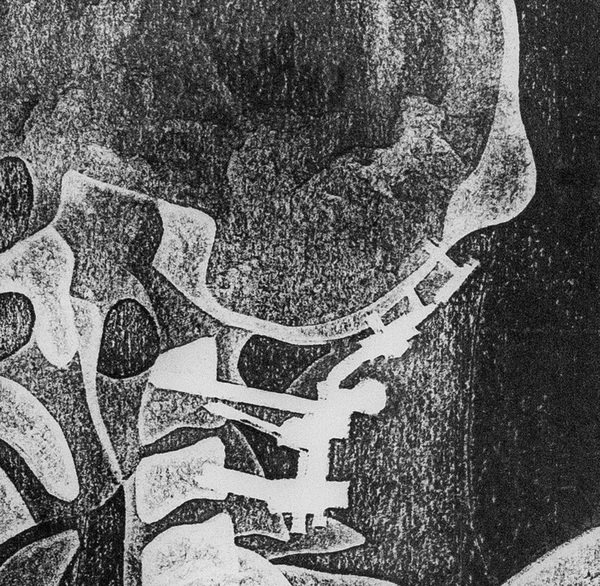

С развитием медицины все больше людей могут позволить себе импланты или металлические конструкции, помогающие работе костей и мышц. Это становится инородным телом внутри человека, что особенно заметно на рентгене. На снимках эти приспособления имеют белый цвет, что значительно отличается по цвету от остальных органов и скелета. Я решила подчеркнуть эти замененные части человеческой опорно-двигательной системы с помощью печати. Для имитации рентгеновского снимка я использовала прозрачный пластик.

Серия состоит из трех работ и выполнена в технике высокой печати. В работе использовалась черная типографская краска и листы прозрачного пластика. Формы для печати вырезались из переплетного картона. Для оформления понадобились белые рамки, светодиодные ленты и листы матового пластика. Все работы выполнены в формате A3.